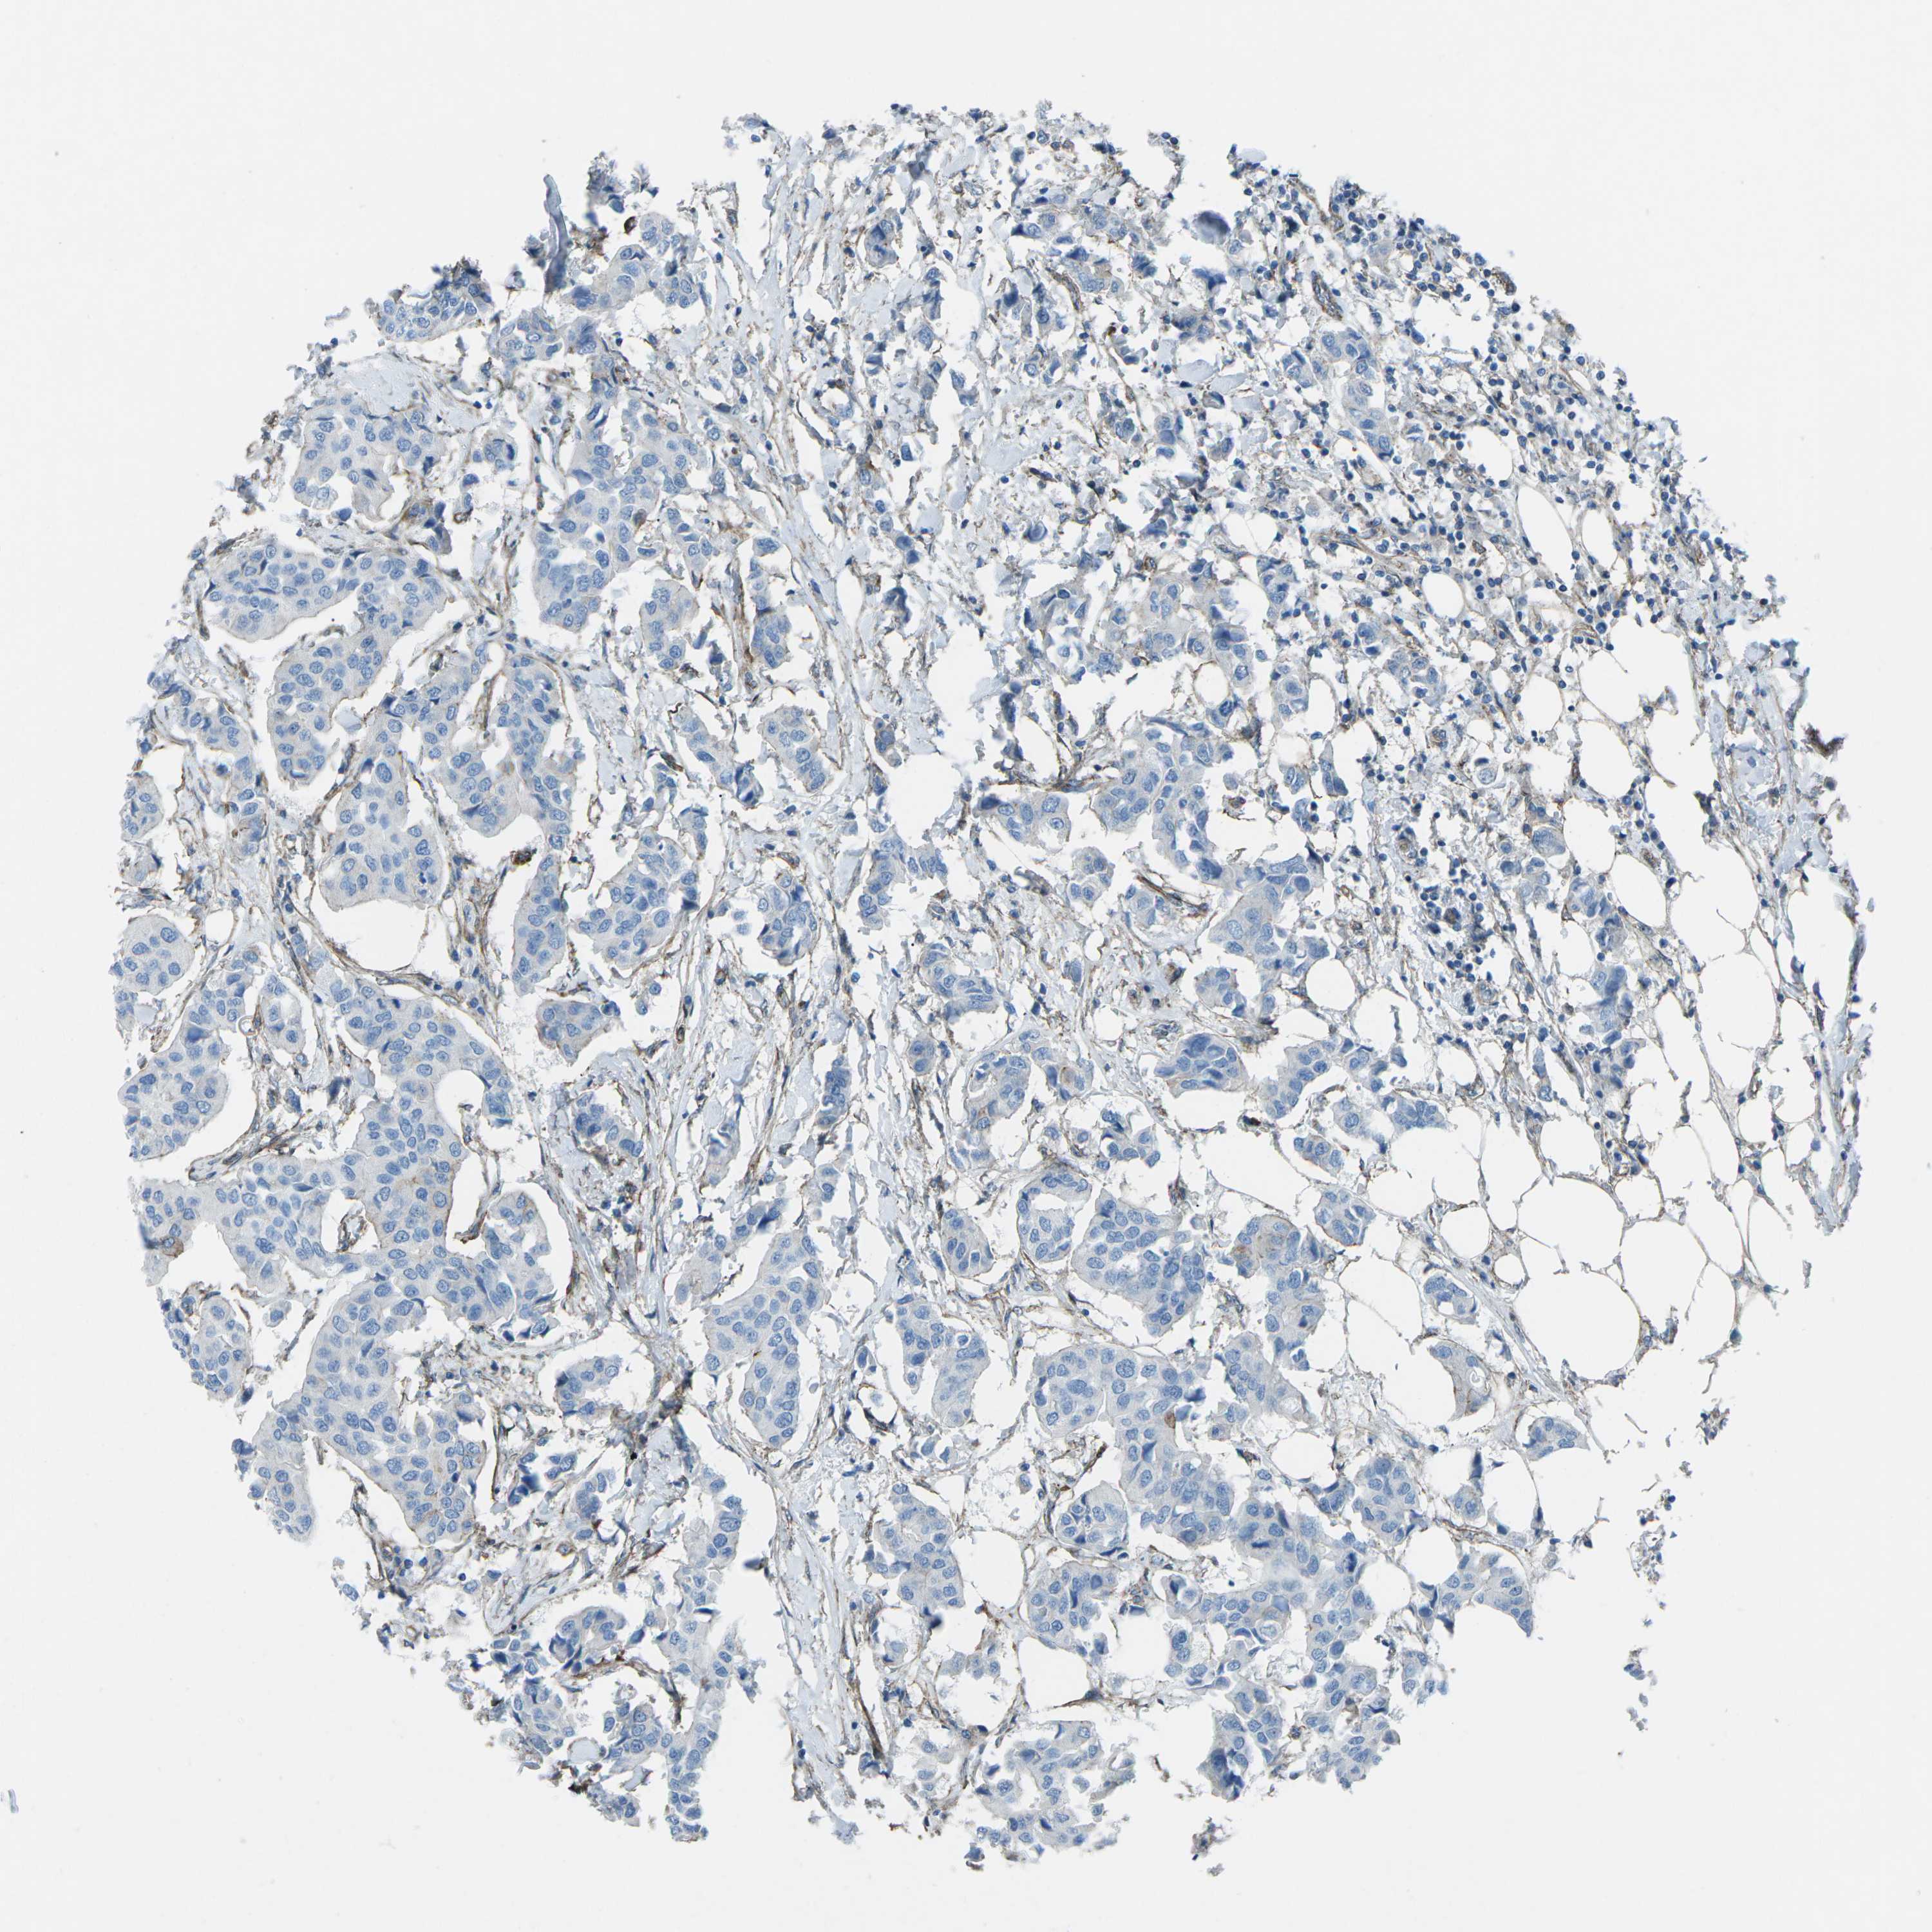

BRCA TCGA BRCA VALIDATION PROTEIN EXPRESSION

ANTIBODIES

AND

VALIDATION